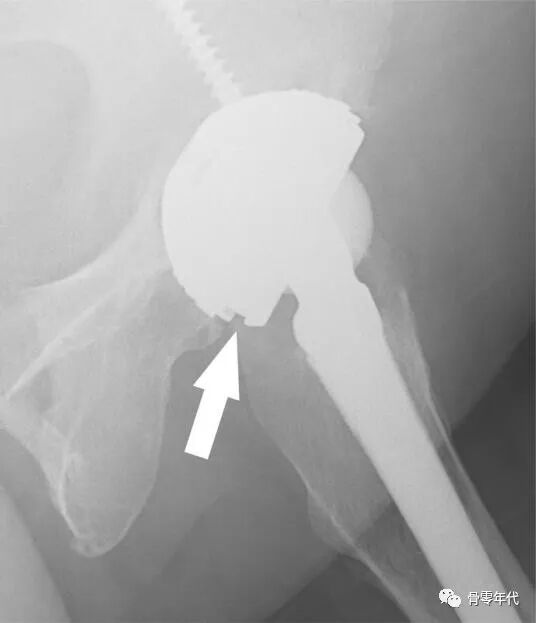

陶瓷内衬背面金属环设计是为了减少陶瓷碎裂的风险,Kwong-Yin Chung认为这种设计的陶瓷杯错位安放率高,35例陶瓷对陶瓷全髋置换术患者资料,采用Trident髋臼系统,术后影像学检查发现,8例陶瓷杯错位安放,其中1例早期手术更换了陶瓷杯,其余7例平均随访14年,没有进行翻修术。运用细致的手术技术,在髋臼壳内实现适当的衬垫对齐,以最大限度地减少这种潜在的可纠正的错误。

x光片显示内衬安装不良,(箭头所指)之间存在间隙